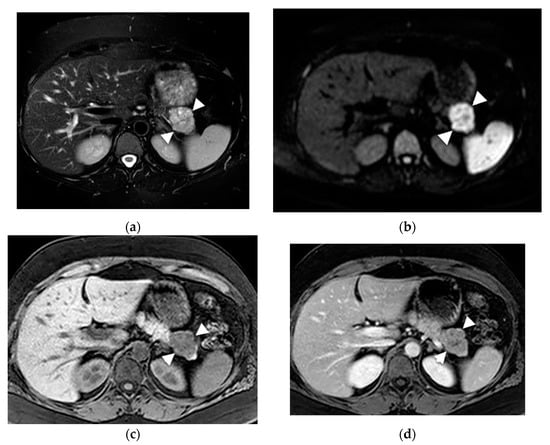

- Mamone, G.; Barresi, L.; Tropea, A.; Di Piazza, A.; Miraglia, R. MRI of mucinous pancreatic cystic lesions: A new updated morphological approach for the differential diagnosis. Updates Surg. 2020, 72, 617–637. [Google Scholar] [CrossRef] [PubMed]